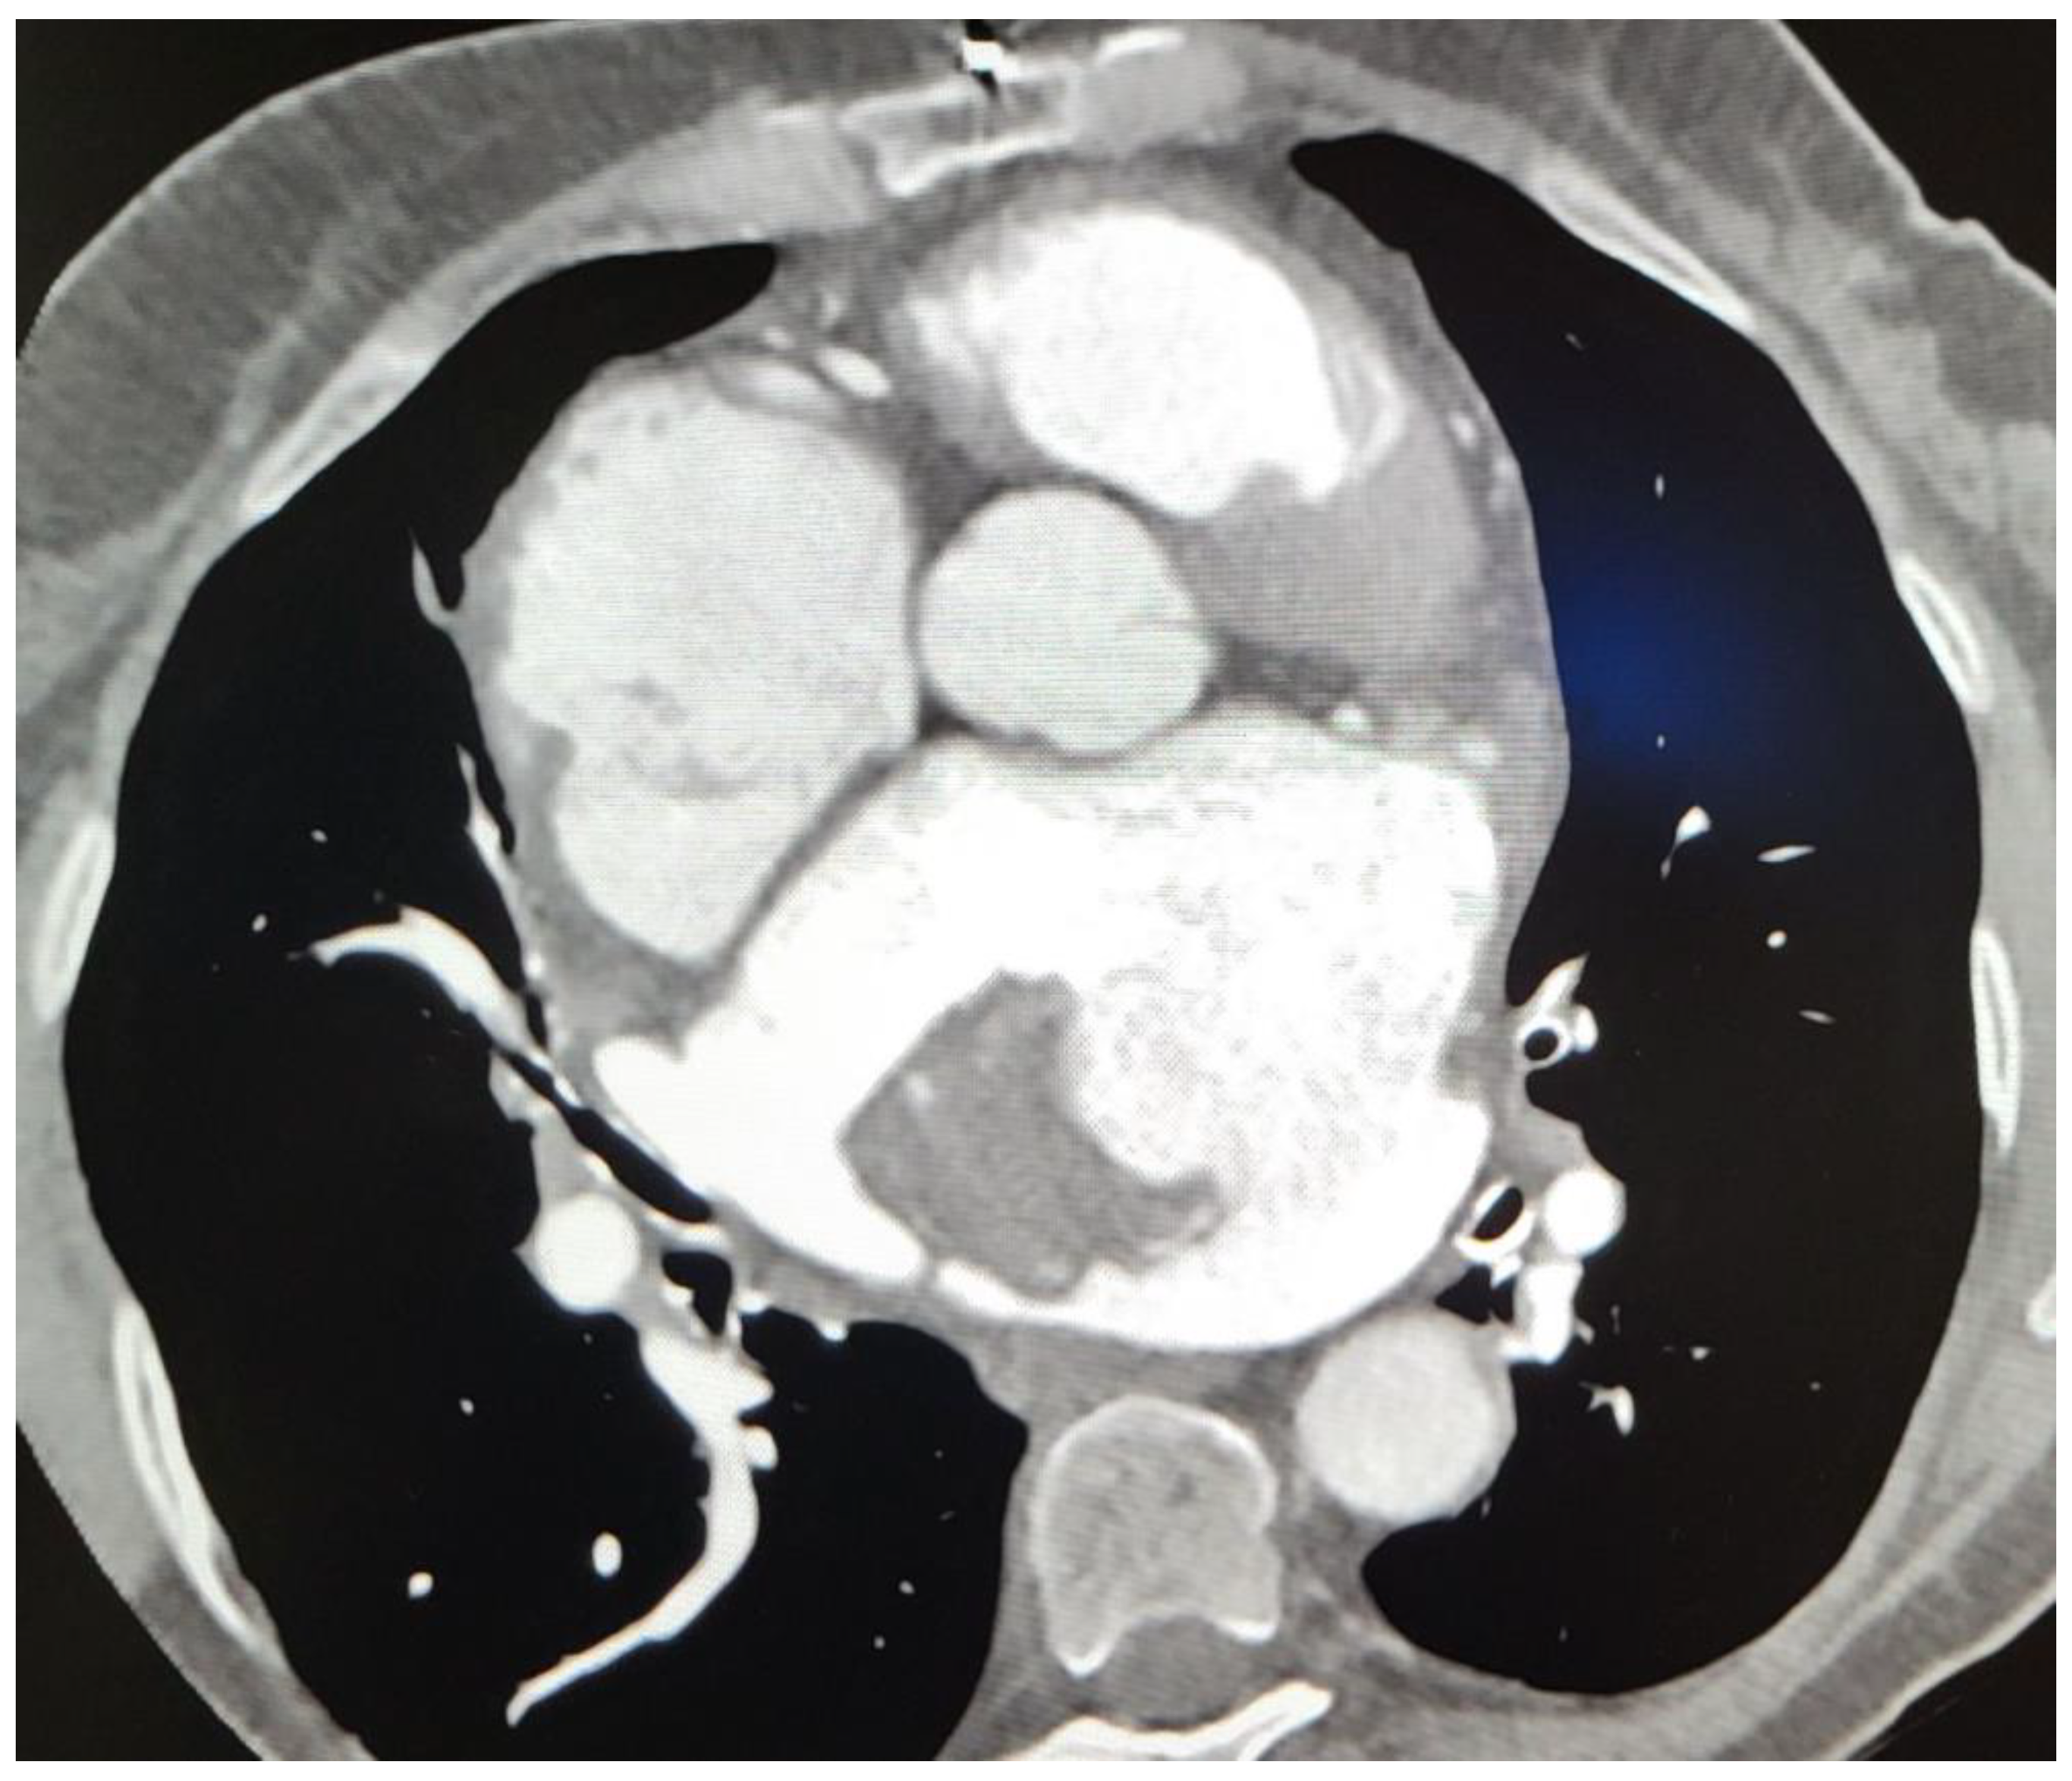

Subsequent CT imaging provided further details, including the mass’s heterodense nature and its vascular connections, raising questions about its origin. On CT, a sharply limited heterodense change with a diameter measuring 53 × 46 × 37 mm with a wide base attached to the wall of the LA was observed (Figure 2). Two branches from the proximal part of the circumflex artery (Cx) were observed, with the first forming a loop that communicated with the auricle of the LA, and the second branch separating at an angle running along the posterior wall of the LA with communication with the structure in the LA (Figure 3). The vascularized mass raised questions regarding its origin, warranting further investigation. Given the diagnosis of moderate to severe mitral stenosis and findings from the cardiac CT that indicated that the right ventricle is in close proximity to the lower third of the sternum and the xiphoid process, the cardio-surgical team opted for a less invasive approach. Considering that this would be a redo operation for the patients, the team decided to first attempt embolization of the lesion to cut off its blood supply, thereby inducing tissue necrosis and subsequent reduction in tissue volume.

Figure 2. Computerized tomography (CT). Sharply limited heterodense change with a diameter of 53 × 46 × 37 mm and a wide base attached to the wall of the atrium.